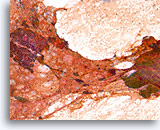

Invasief Ductaal carcinoom, Borst FNA, Celblok.

Met behulp van histologische coupes kunnen in sommige ductale carcinomen invasieve patronen geïdentificeerd worden [4]. Het invasieve patroon bestaat uit ductale cellen die binnen een actieve stroma groeien zonder lobulaire of ductale architectuur. De maligne cellen vertonen geen voorspelbare relatie met stromale referentiepunten en lijken het stroma onder willekeurige hoeken binnen te dringen. De kenmerken van invasiviteit worden in de volgende afbeeldingen geïllustreerd.

40X

Invasief Ductaal carcinoom, Borst FNA, Celblok.

Met behulp van histologische coupes kunnen in sommige ductale carcinomen invasieve patronen geïdentificeerd worden [4]. Het invasieve patroon bestaat uit ductale cellen die binnen een actieve stroma groeien zonder lobulaire of ductale architectuur. De maligne cellen vertonen geen voorspelbare relatie met stromale referentiepunten en lijken het stroma onder willekeurige hoeken binnen te dringen. De kenmerken van invasiviteit worden in de volgende afbeeldingen geïllustreerd.

40X

Invasief Ductaal carcinoom, Borst FNA, Celblok.

Eén residuele, vermoedelijk niet-invasieve melkgang kan worden waargenomen uiterst rechtsboven in de afbeelding (open pijl). Invasiviteit kan worden gediagnosticeerd in de andere onregelmatige, solide, dunne clusters met maligne ductale cellen die het geactiveerde stromaweefsel willekeurig doorsnijden (pijlen).

40x

Invasief Ductaal carcinoom, Borst FNA, Celblok.

Eén residuele, vermoedelijk niet-invasieve melkgang kan worden waargenomen uiterst rechtsboven in de afbeelding (open pijl). Invasiviteit kan worden gediagnosticeerd in de andere onregelmatige, solide, dunne clusters met maligne ductale cellen die het geactiveerde stromaweefsel willekeurig doorsnijden (pijlen).

40x